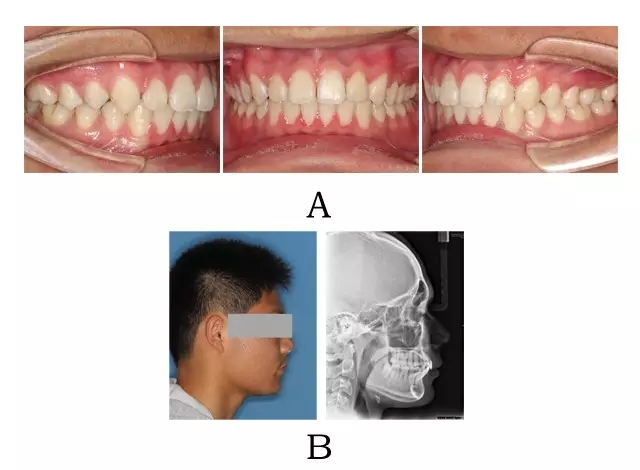

圖 4-3:混合 I 型突面畸形矯形治療臨床療效及頭顱側(cè)位影像變化。

(A) 咬合改善 (B) 側(cè)貌改變

Figure 4-3. Treatment outcomes for merged prognathism (Type I). (A) Occlusion correction. (B)Facial esthetic improvement.